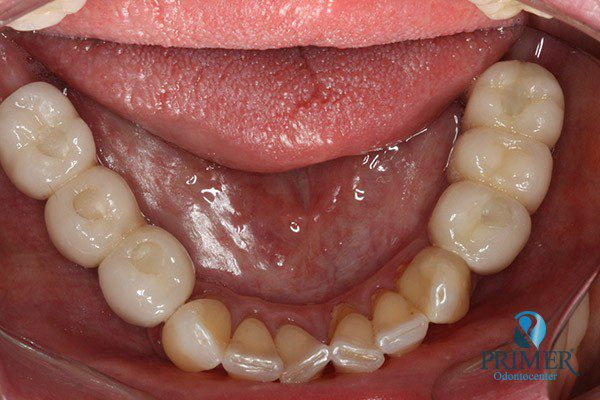

Realizado em: Agosto de 2012Detalhes do tratamento: Implantes instalados imediatamente após extrações de dentes inferiores e prótese fixa sobre implantes (instalada 72 horas após a cirurgia).

- Antes

- Sorriso inicial